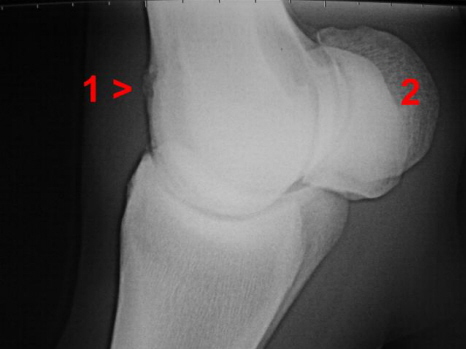

Arthrose Fesselgelenk